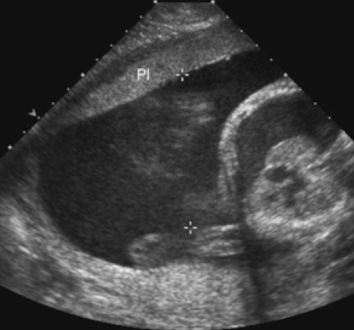

SONO: placenta

homogeneous

pebble-gray—mildly more echogenic compared to uterine wall

may be more echogenic in 1st trimester

smooth borders

highly vascular structure

rim of myometrium outside placenta should be noted

prominent maternal vessels may be seen posterior to placenta (anechoic tubes)

placental lakes may also be seen in placenta